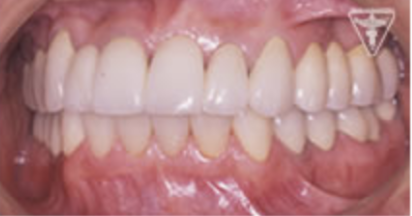

治療後

初期治療を経て歯周外科、歯内療法により病巣の消失が認められ改善された。

右上は将来人工歯根による処置の為GBRを行った。

咬んだ感じが軽くなり、よく咬めると評価を頂きました。